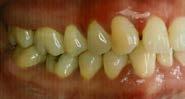

En los estudios intraorales de inicio en las fotografías se muestra en la de frente el diastema anterior, con la línea media dental superior e inferior no coincidentes, la mordida profun da anterior (Figura 2), en la lateral derecha clase l molar y canina bila teral (Figura 3), el apiñamiento leve superior e inferior y la forma de las arcadas.

hacia la derecha y la línea media dental inferior a la izquierda, con mordida abierta anterior, el canino superior derecho se encuentra fuera del arco ( Figura 3 ), en la oclusal superior los inci sivos laterales palatini zados y paladar ojival profundo, en la lateral derecha una relación molar clase II y relación canina no determinable (Figura 4), en la izquier da una relación molar clase I y relación canina no deter minada.